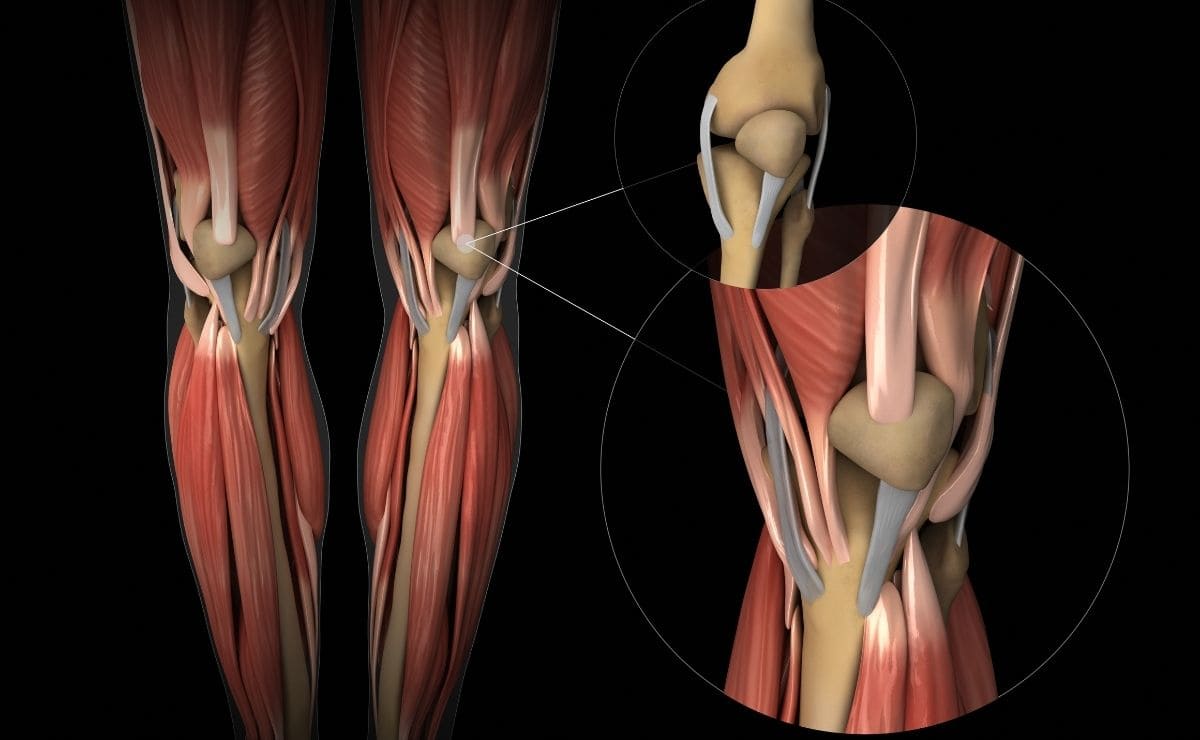

Knowing The Structure Of Tendon Problems And To Cope With It

Olive Nguyen | January 13, 2022 | 0 | Health CareMany people suffer from tendon problems and tendon issues arise due to dreary development, exertion, receptiveness to vibration, mechanical tension, and postponed static position.

Tendon issues occur through a progression of events including a hidden actual issue, followed by degeneration of tendon fibres. Disturbance is only occasionally seen in continuous tendon injury.

Hence the articulation “tendonitis” is a misnomer. The authentic term is “tendinosis.” To retouch, tendons go through three stages: bothering, fix, and overhauling.